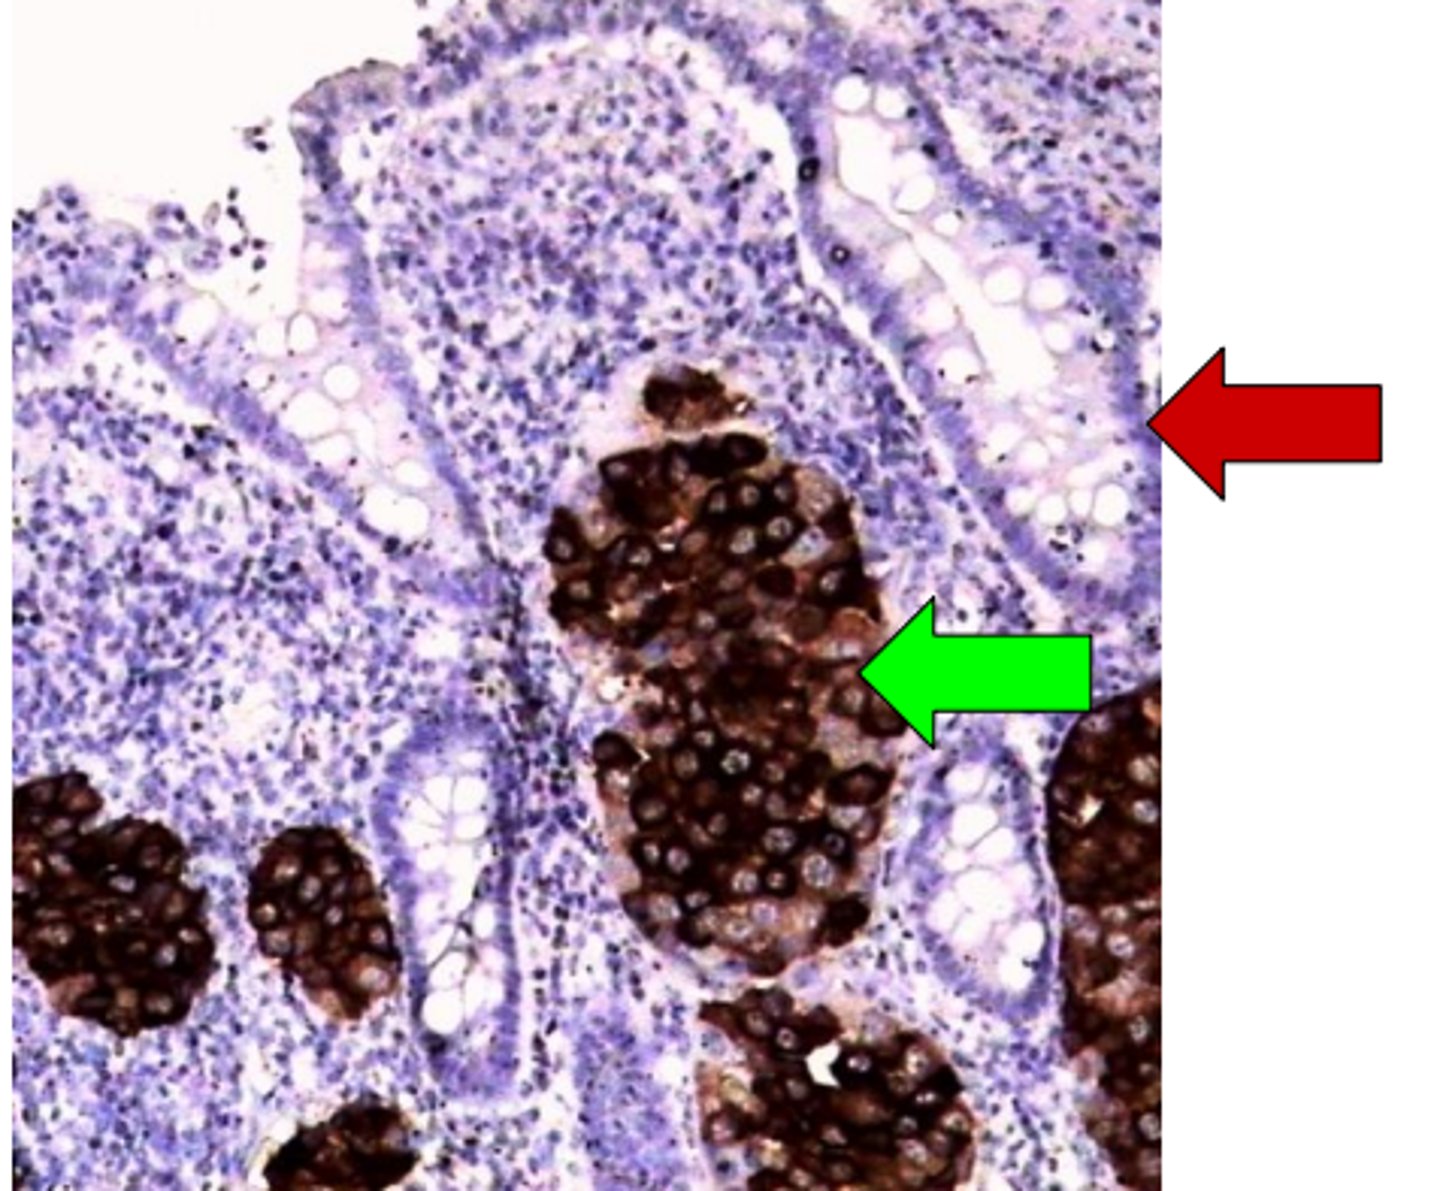

Melanomas metastāze taukaudos (omentā): melanosomu proteīna HMB-45 ekspresija

Melanomas metastāze: HMB-45 ekspresija

Melanomas metastāze zarnas sieniņā. Anti - HMB-45